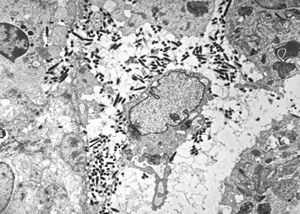

M,54y. | Whipple disease - duodenum